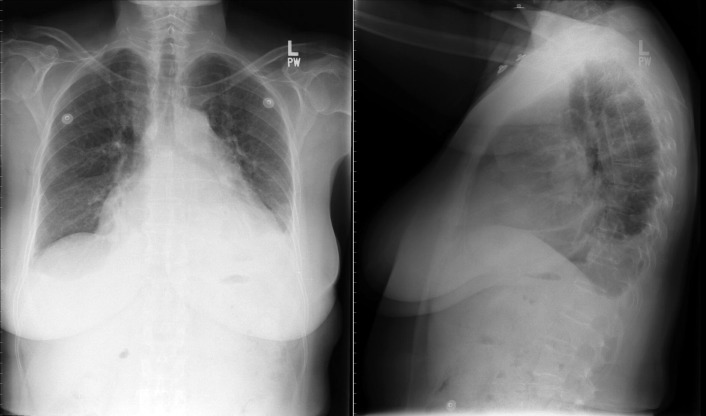

The radiographic findings of mitral stenosis ( Graphic 15-1 ; Figs. 15-1 to 15-16 ) reflect the pressure overload of the left atrium and pulmonary veins, and later of the right heart. As well, the commonly associated chronic atrial fibrillation contributes to (bi)atrial dilation. Associated rheumatic valvular lesions such as mitral regurgitation, tricuspid regurgitation, aortic insufficiency, and aortic stenosis/aortic insufficiency are common, and they alter the appearance of the heart.